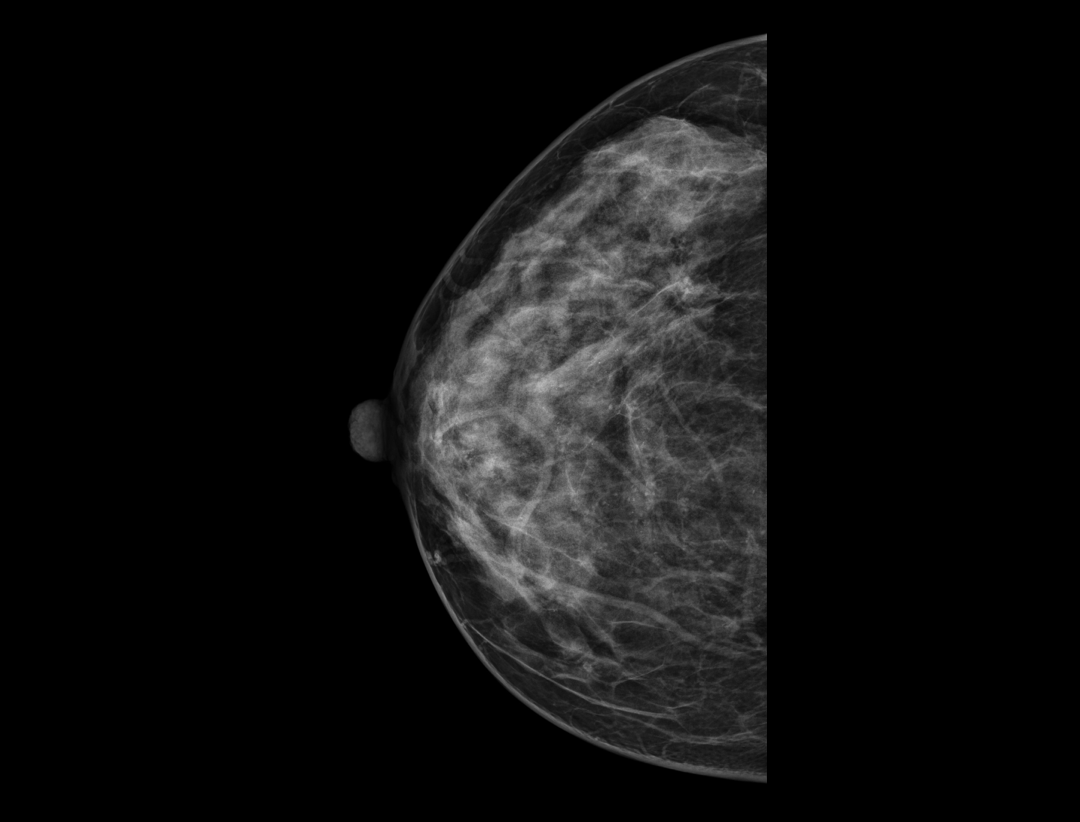

智能乳腺病变分析*

智能辅助病变检测及分析,助力临床诊疗。